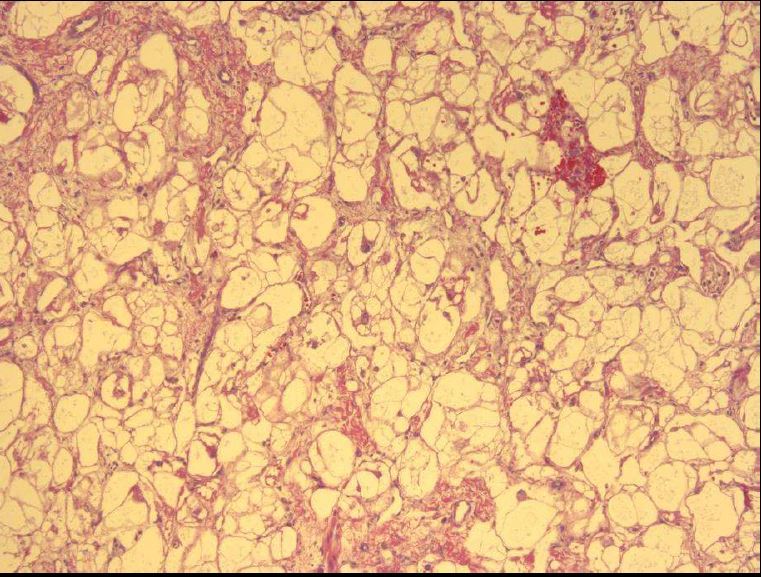

Q

What uncommon disorder is characterized by markedly thin RV replaced by fat?

A

Arrhythmogenic RV Dysplasia